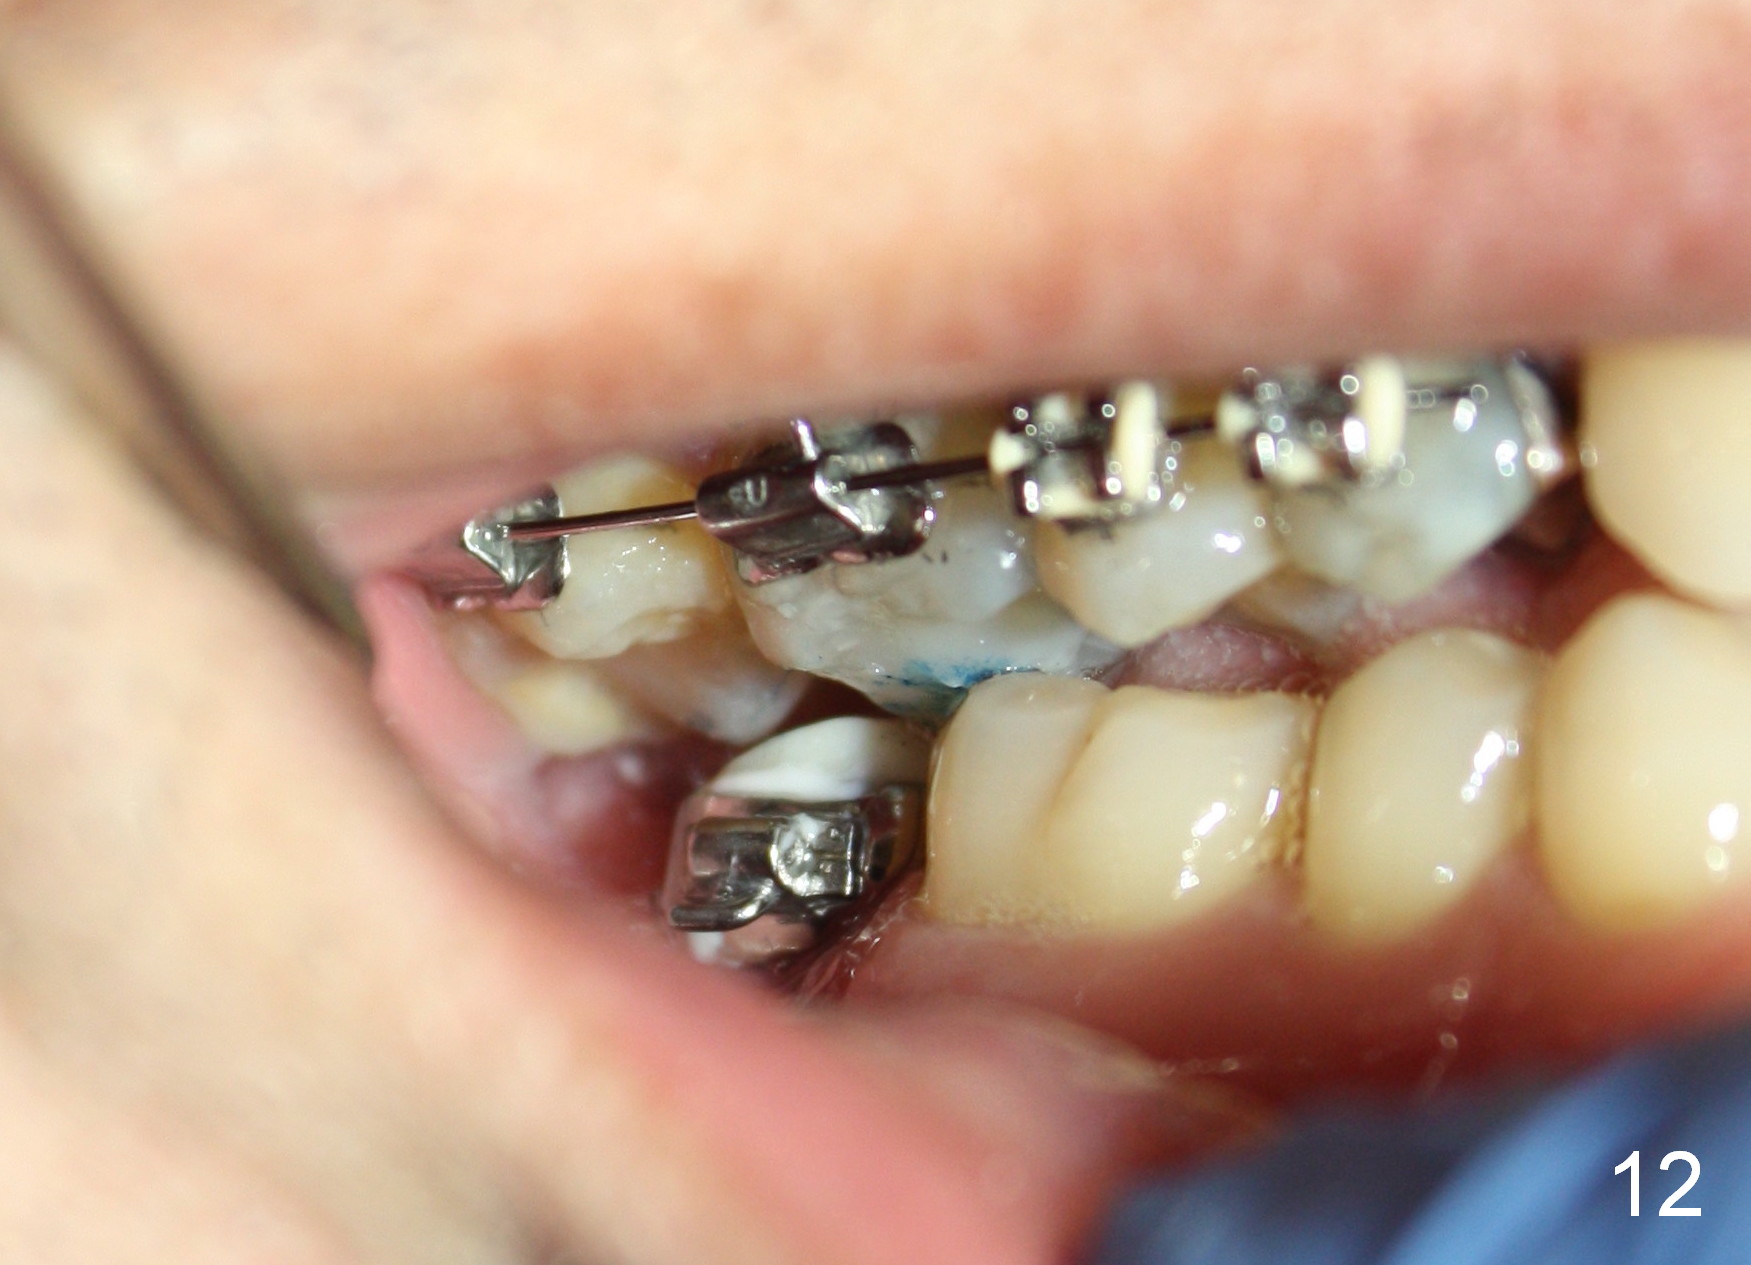

The wound heals uneventfully (Fig.8,9: taken 3 months postop). When an abutment is placed, there is no clearance for a crown. Two mini-implants are placed for the tooth #2 intrusion (Fig.10,11). Four months later, segmental orthodontic appliance is added because of lack of result of intrusion and buccoversion of the tooth #2 (Fig.12). Two months later, all of orthodontic treatment is terminated at the request of the patient. After heavy reduction of the tooth #2, a crown is cemented. Fig.13 (panoramic X-ray) is taken 11 months post cementation. There is no bone loss nearly 3 years post cementation (Fig.14).